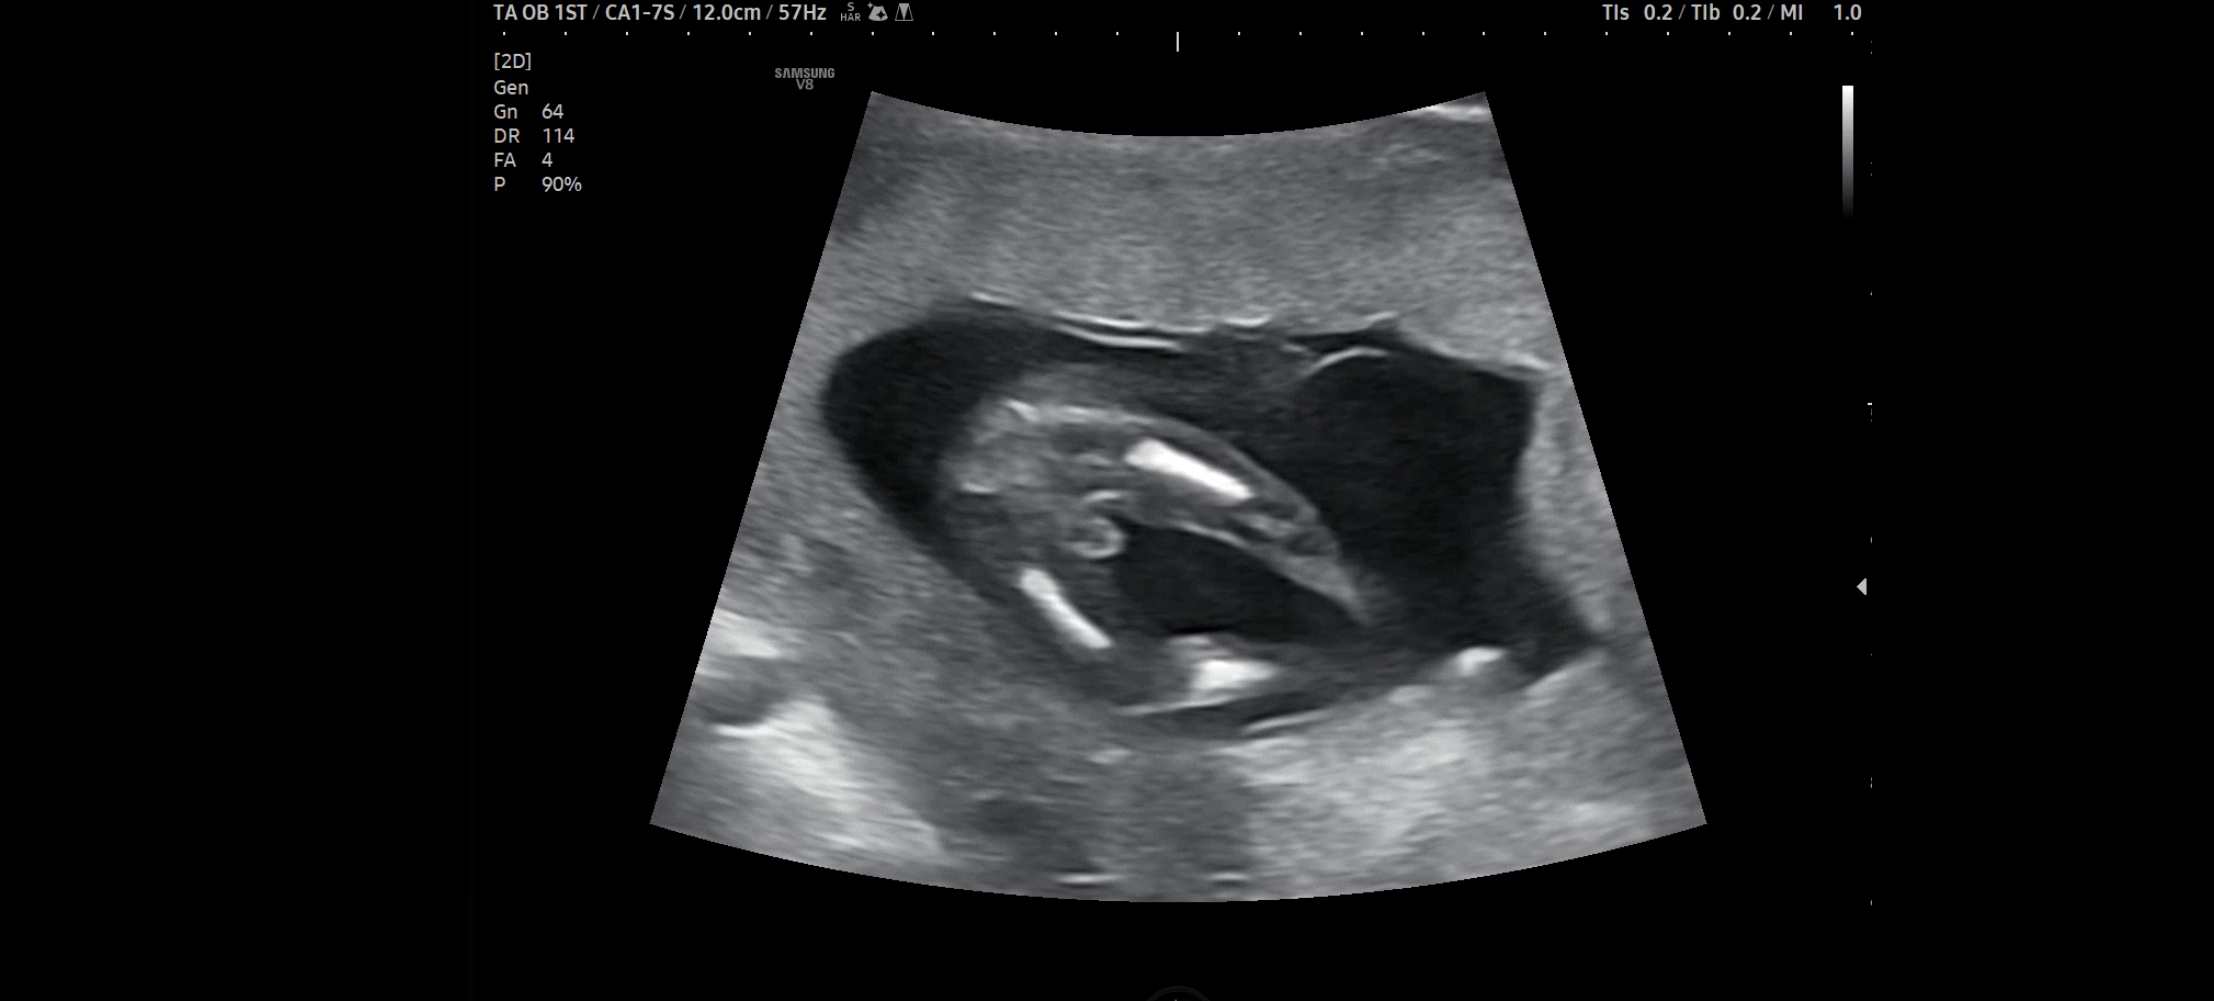

13주3일 초음파 아들....??

오늘 병원가서 초음파 보고왔는데 다리사이에 저거 아들 확정일까요??? 16주까지 더 지켜보자고 하시는데 바뀔수도 있을까요ㅎㅎ...?